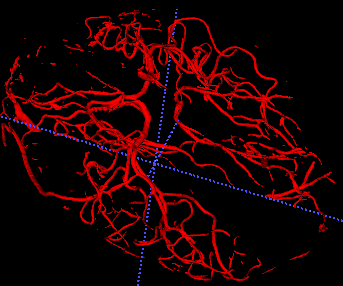

The use of deep learning techniques for 3D brain vessel image segmentation has not been as widespread as for the segmentation of other organs and tissues. This can be explained by two factors. First, deep learning techniques tend to show poor performances at the segmentation of relatively small objects compared to the size of the full image. Second, due to the complexity of vascular trees and the small size of vessels, it is challenging to obtain the amount of annotated training data typically needed by deep learning methods. To address these problems, we propose a novel annotation-efficient deep learning vessel segmentation framework. The framework avoids pixel-wise annotations, only requiring patch-level labels to discriminate between vessel and non-vessel 2D patches in the training set, in a setup similar to the CAPTCHAs used to differentiate humans from bots in web applications. The user-provided annotations are used for two tasks: 1) to automatically generate pixel-wise labels for vessels and background in each patch, which are used to train a segmentation network, and 2) to train a classifier network. The classifier network allows to generate additional weak patch labels, further reducing the annotation burden, and it acts as a noise filter for poor quality images. We use this framework for the segmentation of the cerebrovascular tree in Time-of-Flight angiography (TOF) and Susceptibility-Weighted Images (SWI). The results show that the framework achieves state-of-the-art accuracy, while reducing the annotation time by up to 80% with respect to learning-based segmentation methods using pixel-wise labels for training